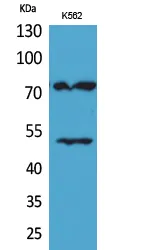

FAK (phospho Tyr397) Rabbit Polyclonal Antibody

Cat: APRab04658

Size1:50μl Price1:$128

Size2:100μl Price2:$230

Size3:500μl Price3:$980

Akt1 (phospho Thr450) Rabbit Polyclonal Antibody

Cat: APRab04215

Size1:50μl Price1:$128

Size2:100μl Price2:$230

Size3:500μl Price3:$980